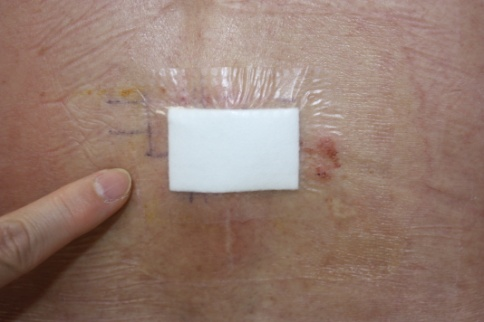

手術後の装具固定

|

腱板修復術後は修復した部分の回復を阻害しないため、一定期間の固定を行います。 腱板修復術を受けられた方は術後3~6週の間、装具を装着して頂きます。 装具の大きさは断裂の程度によって多少異なる場合があります。 図は当院で使用している装具となります。 |

術後約3週間の装具固定期間が過ぎると、徐々に肩関節ならびに肩甲骨の動きの改善を図ります。